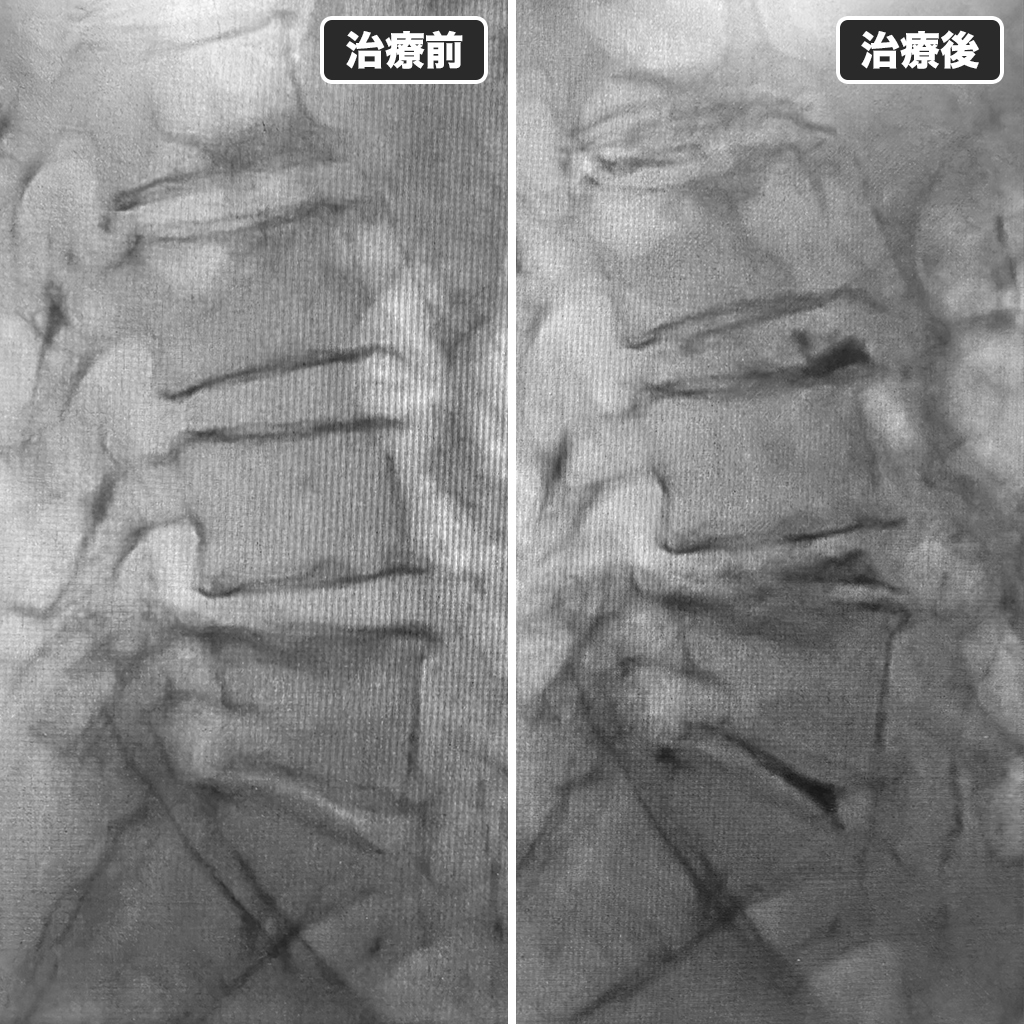

治療前後のレントゲン写真

治療前後のレントゲン写真です。左側が治療前、右側が治療後になります。治療後に腰部に鈍痛が出現しましたが、鎮痛薬を飲んでいただき治まっています。本日も忙しく慌ただしい一日でした。